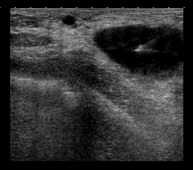

BAG (biòpsia) guiada per ecografia

Biòpsia amb agulla gruixuda o core-biòpsia que consisteix en l'obtenció d'un cilindre de teixit per a l'estudi histològic. Sota control ecogràfic, i prèvia anestèsia local, se situa l'agulla a la zona d'estudi i, a través d'un sistema de tall automàtic, s'obtenen diversos cilindres mil·limètrics de teixit. És un procediment relativament curt i escassament dolorós.

Marcatge amb llavors d'or per a radioteràpia

Consisteix en un marcatge de lesions diagnosticades de càncer per indicar exactament la seva localització amb la finalitat d'aplicar el tractament de repercussió sobre els teixits veïns. Aquest procediment es realitza sota control ecogràfic, amb la localització del tumor i s'introdueixen les llavors d'or (de 3 a 4 llavors) en quatre punts de la seva perifèria.